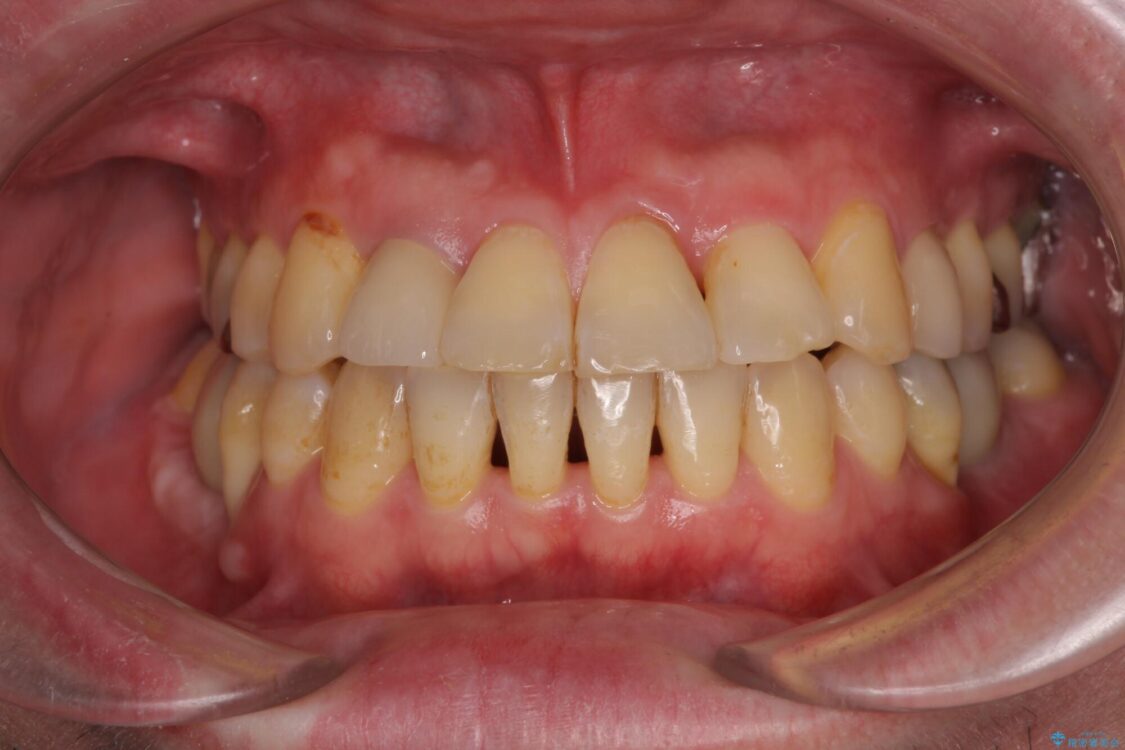

治療後

• 割れてしまった奥歯とデコボコの前歯 矯正治療とインプラント治療 治療後画像

治療後について

骨造成や歯肉移植など、治癒期間の長い処置を必要としたため治療期間は長くなりましたが、安定した咬み合わせと整った歯列となり、患者様には大変満足していただきました。